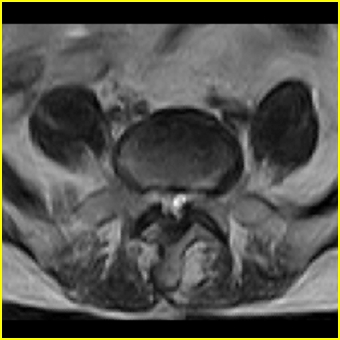

男,78岁,右下肢跛行两月.

右侧黄韧带肥厚或钙化,压迫马尾神经所致。必要时行ct扫描。

腰间盘膨出、黄韧带肥厚、可疑先天性腰椎管狭窄。

退行性病变:增生、椎间盘变性、膨出[l4-5、l5-s1 椎间盘膨出]